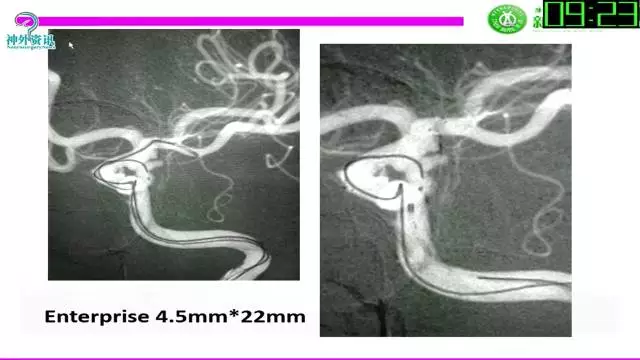

今天为大家分享的是“强生医疗CNV-神经介入专栏”第三十六期,由重庆第三军医大学附属新桥医院神经外科刘俊带来的“Galaxy弹簧圈在不规则动脉瘤中的临床应用”精彩讲课视频及PPT,欢迎观看。文章仅代表作者个人观点,如有不同见解,欢迎同道斧正!